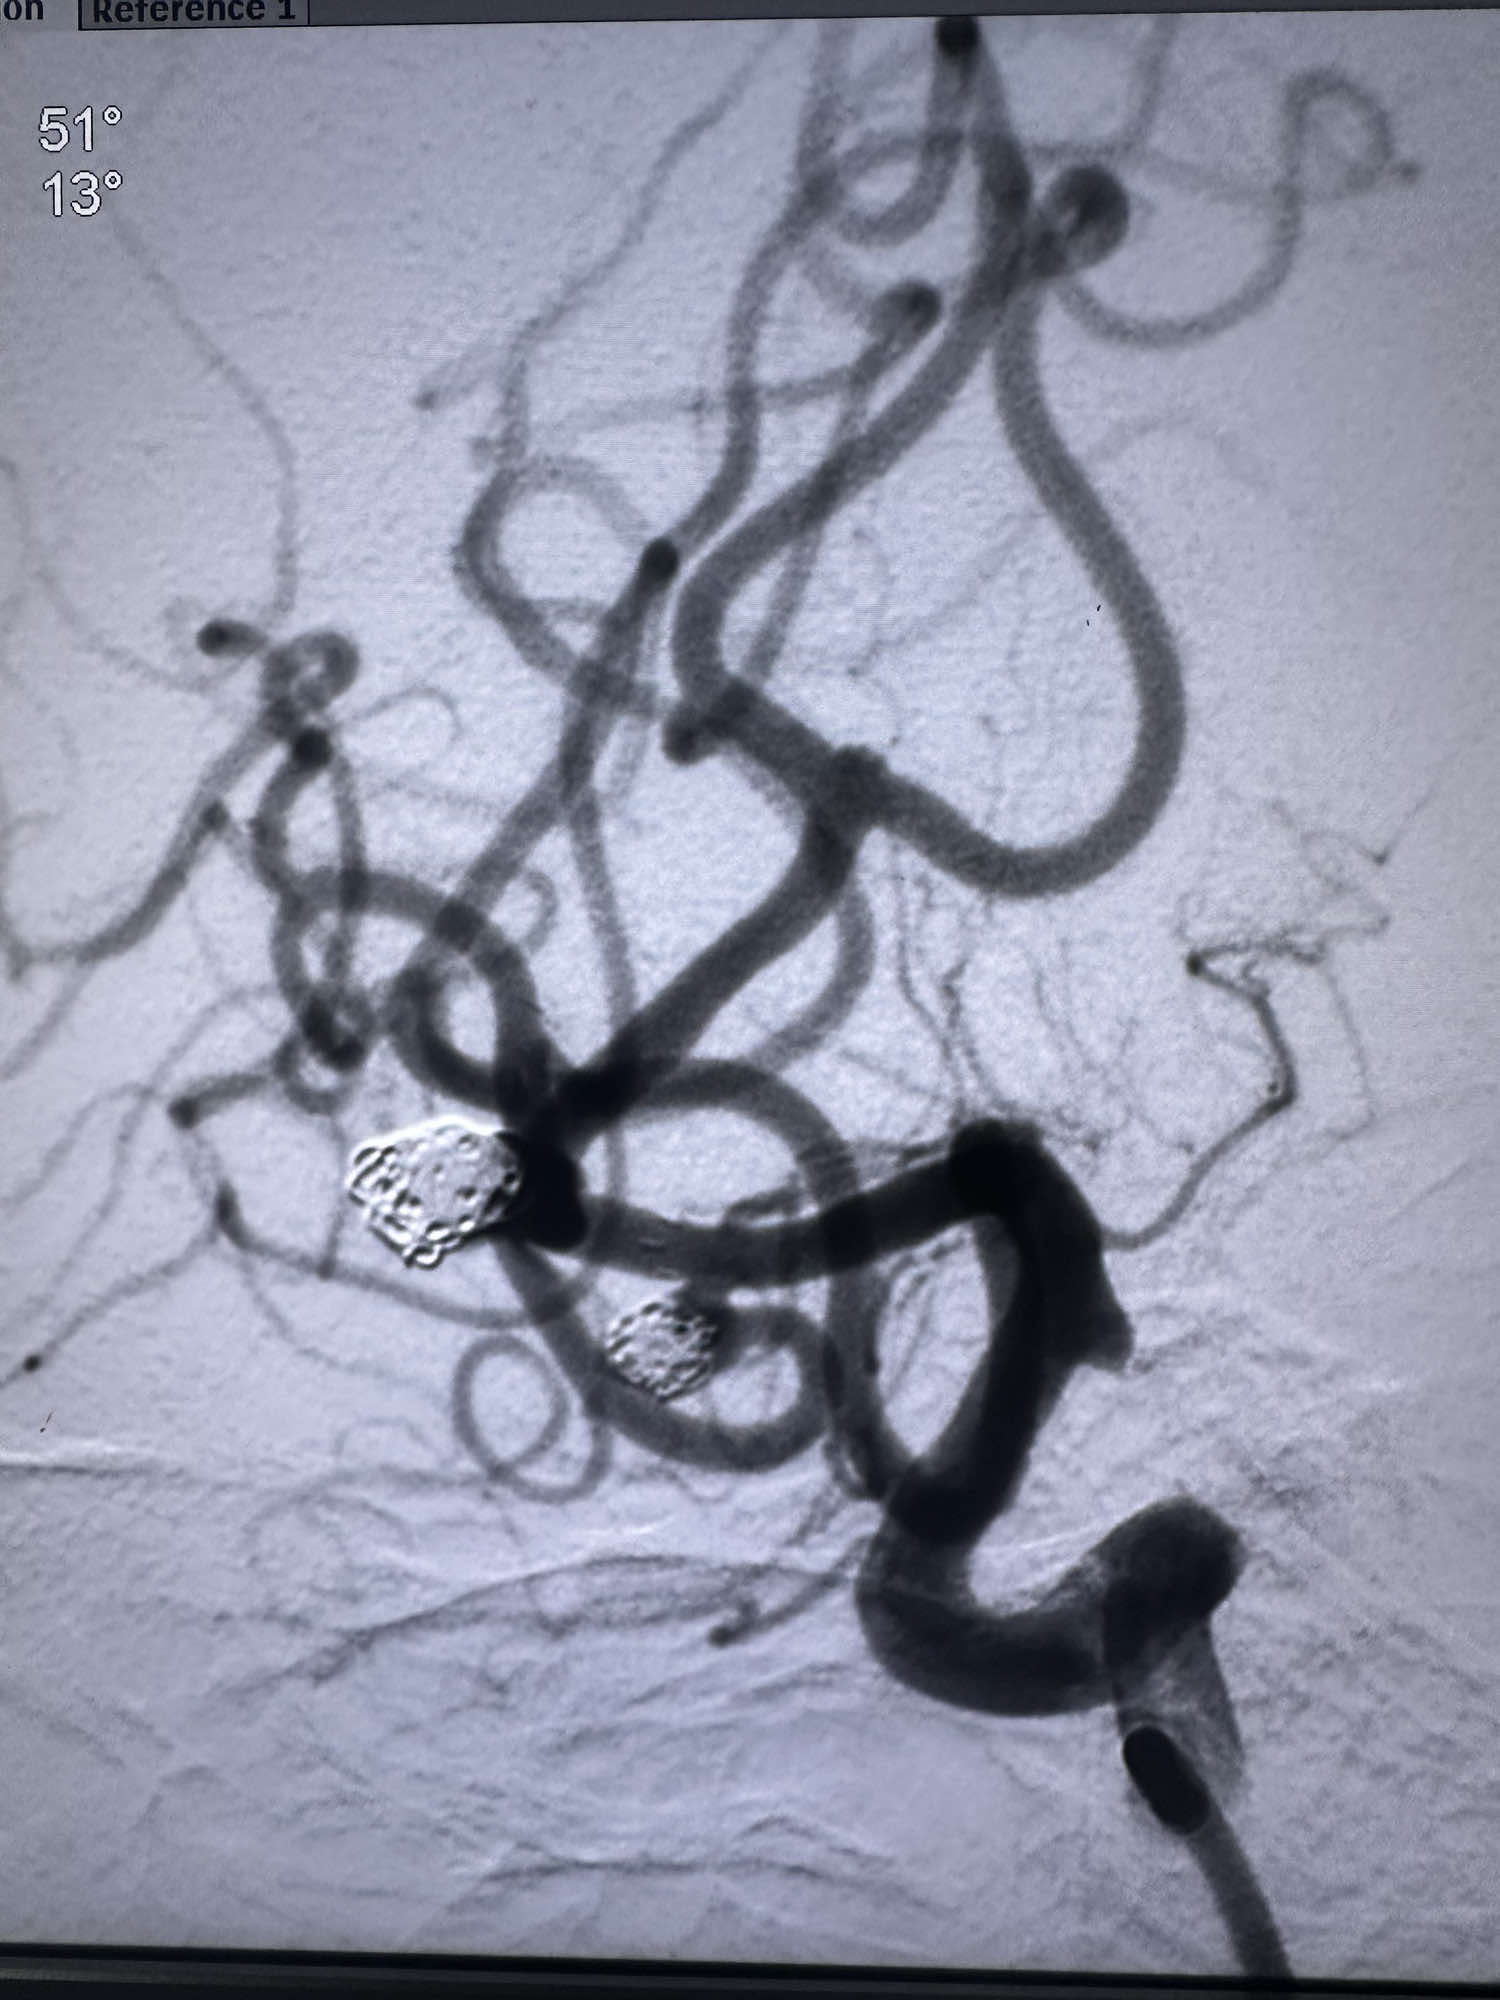

填塞颞下干的动脉瘤时候,本来想支架导管辅助,支架导管(sl-10)双折进入,可惜最后支撑性太差,微导管没有进入颞下干

直接单纯栓塞处理,第一枚圈选择4*8的3D的弹簧圈

后续填入两枚史赛克的弹簧圈

最后骨窗的形态